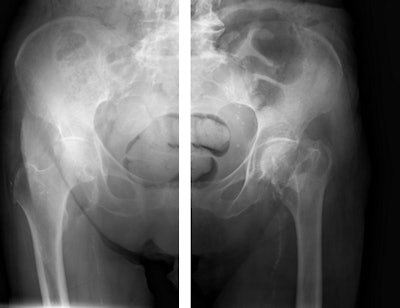

A similar patient-centric approach influenced Siemens' strategy in developing Multitom Rax, a twin robotic x-ray system. The technology has a broad range of potential applications in radiography, orthopedics, angiography, fluoroscopy, and trauma imaging. Indeed, the system is so versatile that it has been described as "radiology's answer to the Swiss army knife" by clinicians at Erlangen University Hospital in Germany, where the first system was installed in October 2015.

The system has two ceiling-mounted arms, one of which supports the x-ray tube and the other carries the 43 x 43 cm flat-panel detector. The robotic technology allows both arms to be moved automatically while fine adjustments can then be made manually by the operator.

"The precise positioning of the arms in all three planes makes the examination so much easier, regardless of whether the patient is standing, sitting or lying down. Our strategy is based on the principle that the system moves, not the patient, which reduces the risk of additional injuries and pain," explained Francois Nolte, head of the company's x-ray products business line.

The machine can record static, dynamic, and real-time 3D sequences, and the full range of its potential applications is still to be explored. But there are clinical applications in which it already appears to have advantages over CT, notably in investigations of upper limb fractures in obese patients and weight-bearing lower-limb bone examinations of diabetics, he added.